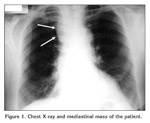

A 63-year-old woman visited her physician because of 3-months history of headache and fatigue. She denied changes in her voice, dyspnea, dysphagia, or musculoskeletal pain. There was no relevant medical or family history. Physical examination was normal. Abnormal calcium and phosphate levels were detected in blood analysis and abnormal right upper mediastinal shadow on chest x-ray film was detected (Figure 1).

Figure 1